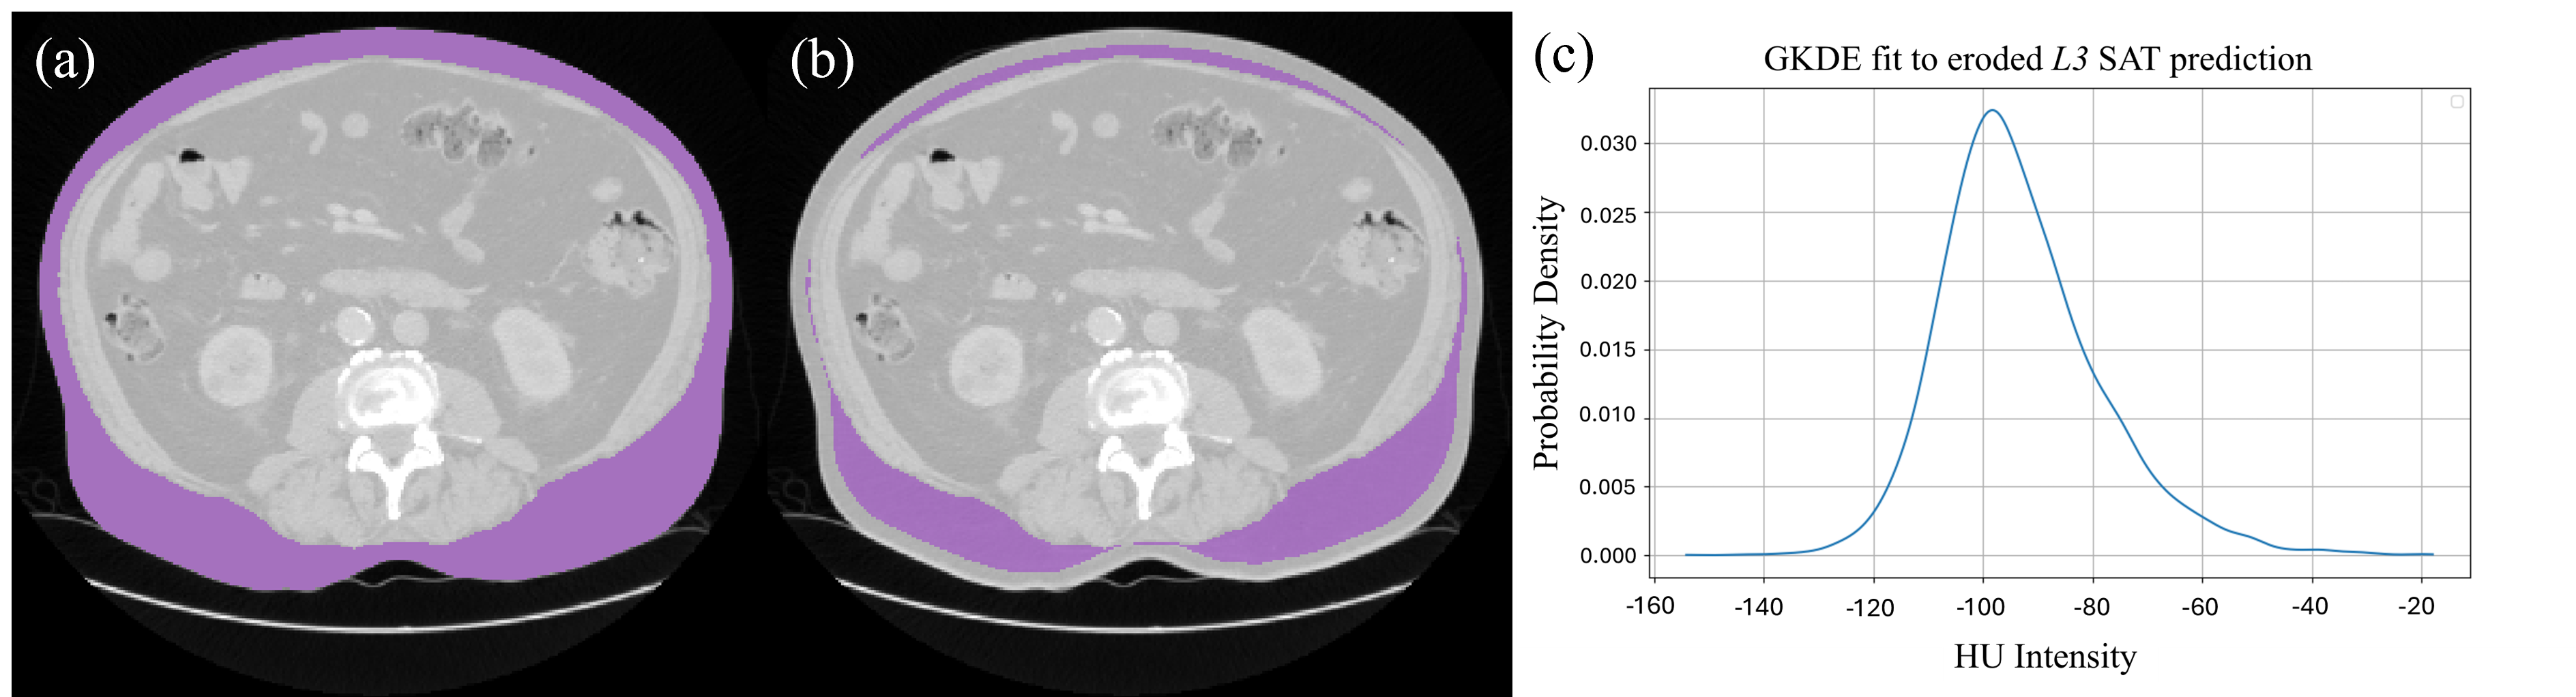

Refer to caption

Figure 3: (a) An axial CT slice at the predicted L3 level with predicted SAT (purple) mask. (b) The same CT with the SAT mask eroded to 20%percent2020\%20 % of its original area. (c) A visualisation of the GKDE fit to the eroded SAT mask.

Following semantic segmentation, GKDE analysis is applied to the SAT predictions to refine the organ-free abdominal cavity mask and accurately segment VAT. Before fitting a GKDE to the SAT prediction, adjustments are necessary due to the inclusion of the cutis (the dermis and epidermis) in the SAROS ground-truth annotations. As the cutis is not AT, its intensity values do not accurately reflect those of SAT. Additionally, false positive predictions of SAT may predict voxels which are outside the body, further affecting the PDF estimated by the GKDE. To account for this, we erode the SAT prediction’s outer layers at the L3 vertebral level, taken to be the median z𝑧zitalic_z coordinate of the L3 prediction, until the mask is at 20%percent2020\%20 % of its original size. The GKDE is then fitted to the intensity values of this eroded mask. Fitting the GKDE to this axial prediction, as visualised in Fig. 3, instead of the volumetric SAT prediction is chosen for computational efficiency.

The full KEVS deployment utilising semantic segmentation, SAT erosion, GKDE fitting, and VAT mask prediction is visualised in Fig. 1. The PD percentile used in KEVS was 15%percent1515\%15 %, chosen as this threshold best balances metrics performance, as shown in Online Resource 1 Fig. 1.